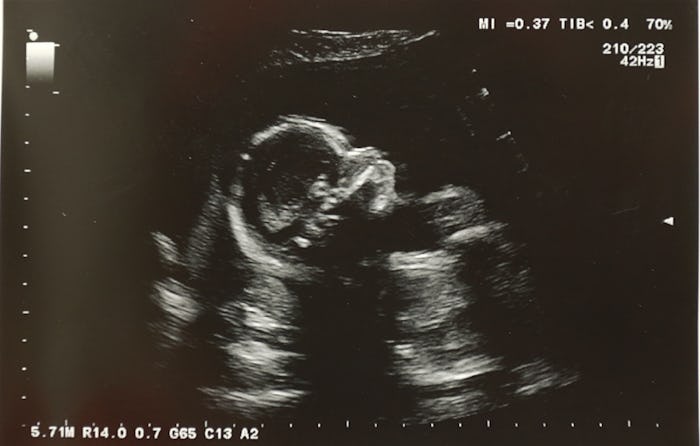

I just want my baby to be OK, I repeated over and over again on a Thursday morning last April. Three weeks earlier, a sonographer had seen an abnormality in my unborn daughter’s brain. At 28 weeks gestation, her lateral ventricles were double normal size (these are important because they carry cerebral spinal fluid to her spinal cord). This type of inflammation, known as ventriculomegaly, is associated with a number of developmental disorders. After three weeks of diagnostic Level 2 ultrasounds, blood tests, and MRIs and three weeks of doctors speculating about possible viral infections, hydrocephalus, and shunts, we were finally going to get some answers. But that ultrasound effectively ruined the vision I had created for myself of a happy, healthy pregnancy producing a happy, healthy baby. My 28-week ultrasound confirmed my worst nightmare and it threw everything into complete chaos.

We arrived at the hospital and were immediately taken to an exam room. The doctor, one of the best in the field of fetal and maternal health in our city, was soft-spoken and kind. He immediately put me at ease and again, I knew, everything would be fine. As he squirted the gel on my belly and pressed the wand over the baby, I felt confident. Brave. My daughter moved constantly inside of me and always kicking. Sick babies weren’t that active, I told myself. We’d had enough ultrasounds to see her cute little nose, her kissable little mouth. We'd watched her grow for seven months. Unhealthy babies didn’t grow like weeds.

I knew — I was sure — she was going to be fine. The doctor finished the scan, wiped the goo off my belly, and helped me sit up. Then he asked us to meet him in the Consultation Room.

Here is something I now know to be a universal truth: When a doctor asks to speak to you in a Consultation Room, everything is not going to be fine. The room was small and white with an old, green pleather couch and requisite faded watercolor prints on the wall. My partner and I held hands and tried to remain positive. But the confidence I'd felt earlier was fading fast. Our daughter had agenesis of the corpus callosum.

Agenesis of the corpus callosum is a congenital birth defect that affects seven in 1,000 births, though it is impossible to know the true occurrence of callosal disorders because the prognosis varies drastically from person to person. While some people may experience severe cognitive and developmental delays, others may not seem affected at all, and they'll go on to live a completely “normal” life. On top of all the other unknowns, it's impossible to predict how a person’s agenesis will affect them. That not knowing terrified me. ACC can be partial – underdeveloped, but present — or complete, which means it's totally absent from the brain. Our daughter’s was complete.